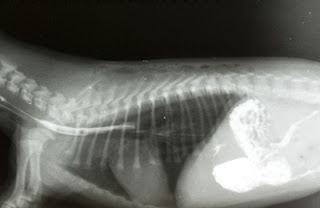

Descripción: Cuando el feto hospedador consigue sobrevivir al parto, éste puede mostrar un abombamiento en la zona donde se sitúe el feto parásito. El 80% de las veces se encuentra en la región abdominal, pero también puede encontrarse en el cráneo, zona sacra, escroto…. También puede pasar desapercibido al principio. Más tarde, conforme la persona va creciendo también lo hace el feto parásito.

Al realizar pruebas de imagen se observan órganos en lugares donde no deberían existir aunque también pueden verse unas diminutas piernas, brazos, dedos, pelo o cualquier otro elemento del feto que haya desarrollado. No hay dos casos iguales de fetus in fetus, puesto que los fetos parásitos pueden situarse en zonas muy distintas del feto hospedador y, por tanto, también será diferente el grado de crecimiento y elementos que haya llegado a desarrollar. Hay fetus parásitos muy desarrollados y otros que sólo poseen un número escaso de órganos.